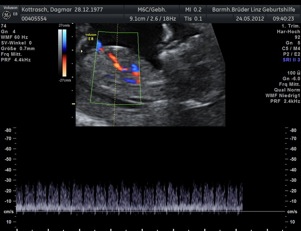

* First Trimester Screening. Messung der Nackentransparenz, Nasenbein, Combined Test (12.-14. SSW) - hier Termin vereinbaren!

Neben den ganz normalen MUKIPA-Untersuchungen liegt der Schwerpunkt der gynäkologischen Wahlarztpraxis in der Ultraschalldiagnostik,

d.h. pränataler Ultraschall (Messung der Nackendicke, Organscreening) einerseits, andererseits kann noch eine Untersuchung mittels 4D-Ultraschall durchgeführt werden,